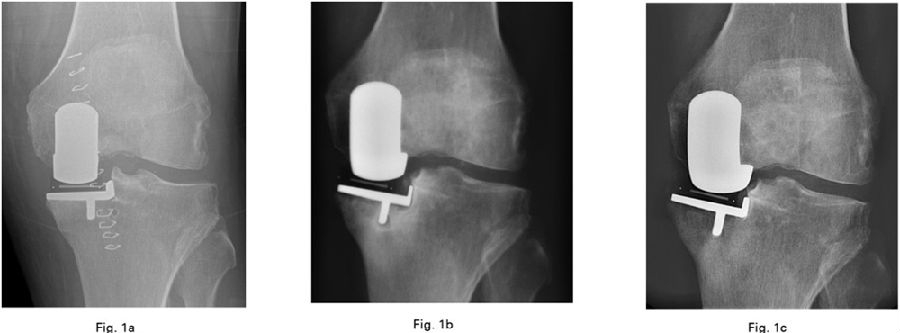

假体组件的位置:内外侧

开髓点偏内侧,在股骨内髁外侧线的延长点向上10mm左右的位置,在后交叉韧带止点的前方钻开髓孔,用手将髓内杆推入,避免用鼓槌敲,以免变线导致股骨假体位置不好。

股骨钻孔方法:插入髓内杆,插入导向器并设置为G型夹所选厚度,插入连接器以确保10°屈曲,保证6mm孔(股骨柱)在股骨髁正中间,避免前内侧悬出,注意导向器的外侧移动。钻孔的位置直接决定假体的位置。

可以通过解剖定位法确定这两个孔的位置,即是在股骨内髁的中线上用电刀画线,两个孔刚好在这条线上为合适,注意画中线的时候要现将内侧髁间窝骨赘去除,此时线才是准确的。另外还可以通过胫骨假体确定股骨假体位置,在胫骨假体正中间在胫骨上标记线并向股骨髁上延长,将胫骨假体和股骨假体对正。